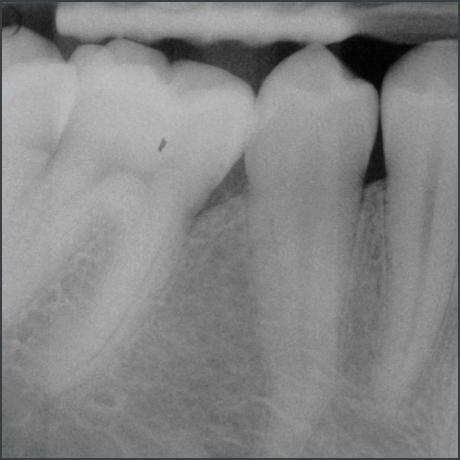

Before treatment with Straumann® Emdogain®.

Courtesy of Prof. Carlos Nemcovsky